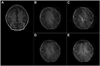

Blood oxygenation level dependent (BOLD) functional magnetic resonance imaging (fMRI) is commonly performed using 2D single-shot echo-planar imaging (EPI). However, single-shot EPI at 7 Tesla (T) often suffers from significant geometric distortions (due to low bandwidth (BW) in the phase-encode (PE) direction) and amplified physiological noise. Recent studies have suggested that 3D multi-shot sequences such as PRESTO may offer comparable BOLD contrast-to-noise ratio with increased volume coverage and decreased geometric distortions. Thus, a four-way group-level comparison was performed between 2D and 3D acquisition sequences at two in-plane resolutions. The quality of fMRI data was evaluated via metrics of prediction and reproducibility using NPAIRS (Non-parametric Prediction, Activation, Influence and Reproducibility re-Sampling). Group activation maps were optimized for each acquisition strategy by selecting the number of principal components that jointly maximized prediction and reproducibility, and showed good agreement in sensitivity and specificity for positive BOLD changes. High-resolution EPI exhibited the highest z-scores of the four acquisition sequences; however, it suffered from the lowest BW in the PE direction (resulting in the worst geometric distortions) and limited spatial coverage, and also caused some subject discomfort through peripheral nerve stimulation (PNS). In comparison, PRESTO also had high z-scores (higher than EPI for a matched in-plane resolution), the highest BW in the PE direction (producing images with superior geometric fidelity), the potential for whole-brain coverage, and no reported PNS. This study provides evidence to support the use of 3D multi-shot acquisition sequences in lieu of single-shot EPI for ultra high field BOLD fMRI at 7T.